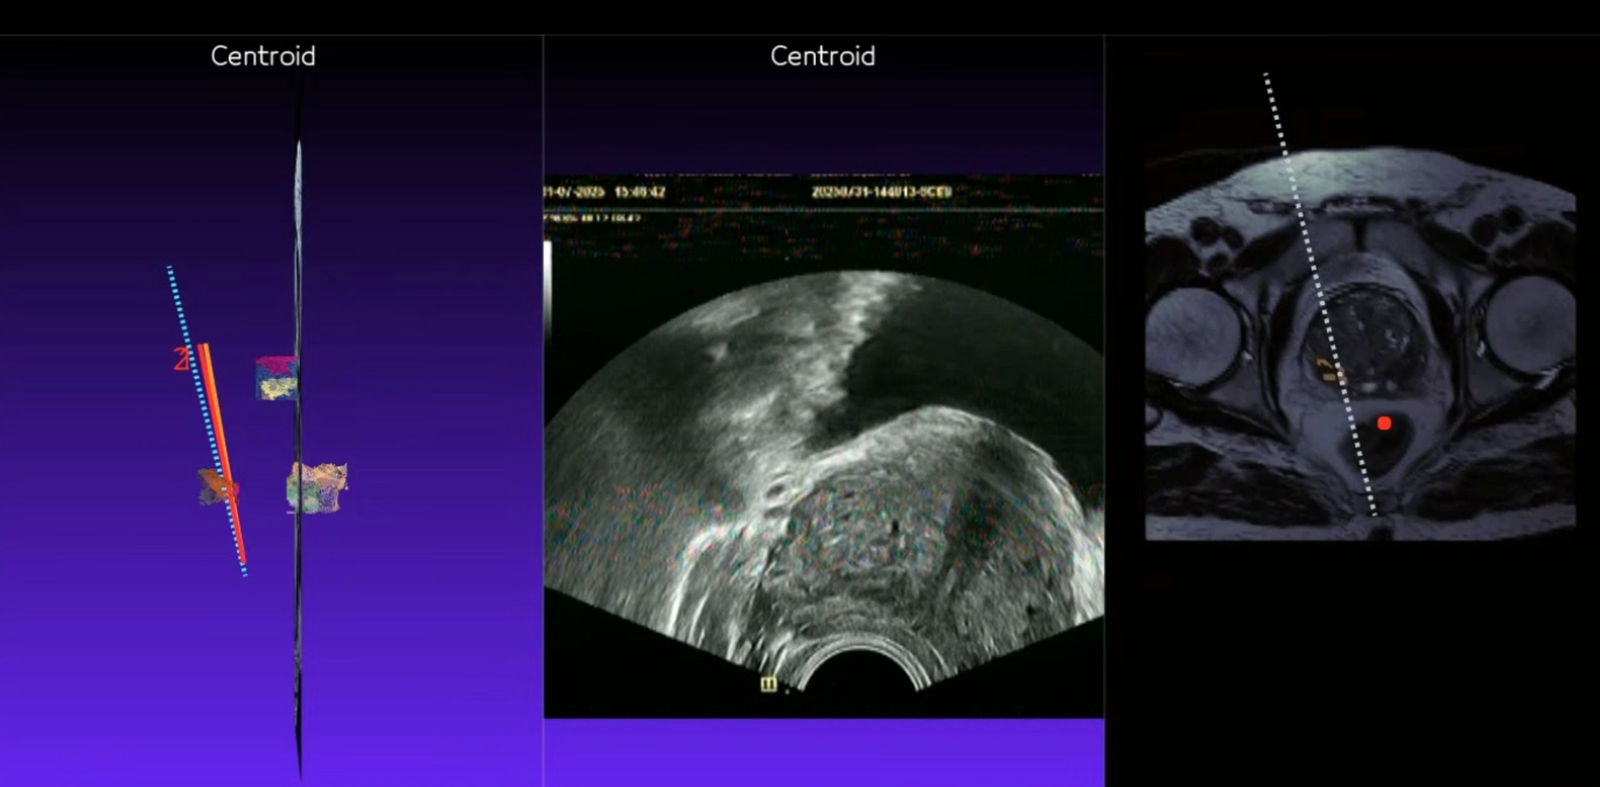

Prostat Füzyon Biyopsi

MR görüntüleri ile ultrason görüntülerinin birleştirilerek hedefe yönelik biyopsi yapılmasını sağlayan akıllı bir teknolojidir.

MR ve ultrason görüntüleri birleştirilir, **robotik sistemle** şüpheli hedeflerden hassas ve isabetli örnekler alınır.